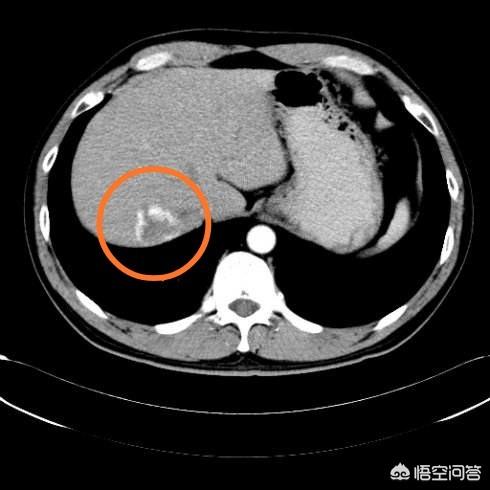

下は私が今まで見た中で最大の肝血管腫で、16cmの大きさ、54歳の女性、心窩部痛のために受診した。

大きな血管腫とは、大きさが5cmを超えるもので、肝臓領域の痛み、肝機能異常、肝臓の端に位置する血管腫など、著しい圧迫を伴う症状を呈するものである。上記のような症状があり、大きさが16cmの女性患者は積極的な治療が必要である。